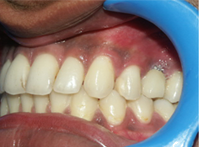

Your child has a beautiful set of teeth as a toddler but as he grows into adolescence you begin to notice an irregular arrangement of teeth. The canine teeth at the corner of the mouth looks especially irregular which looks distasteful.

Two different problems - In the case of the child irregular arrangement of teeth not only looks unsightly but also makes the cleaning of teeth difficult. In the case of the office assistant the protruding teeth results in a lower self esteem. Both the result of the improper position of teeth or jaws.

Irregular Teeth

Correction of Crowding

Teeth which are irregular can be straightened by Orthodontic treatment which if severe might require removal of teeth.